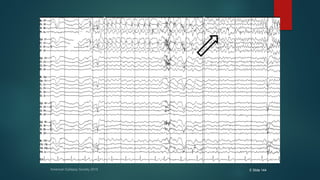

American Epilepsy Society 2015 E Slide 144

๏ต Left temporal onset seizure discharge with onset showing rhythmic

delta localized to the left anterior temporal region, with phase-

reversal noted over the F7-T7 and F9-T9 derivations

๏ต Discharge evolves into rhythmic left temporal theta towards end of

the epoch shown.

๏ต Left temporalonset seizure discharge with onset showing rhythmic delta localized to the left anterior temporal region, with phase- reversal noted over the F7-T7 and F9-T9 derivations ๏ต Discharge evolves into rhythmic left temporal theta towards end of the epoch shown.